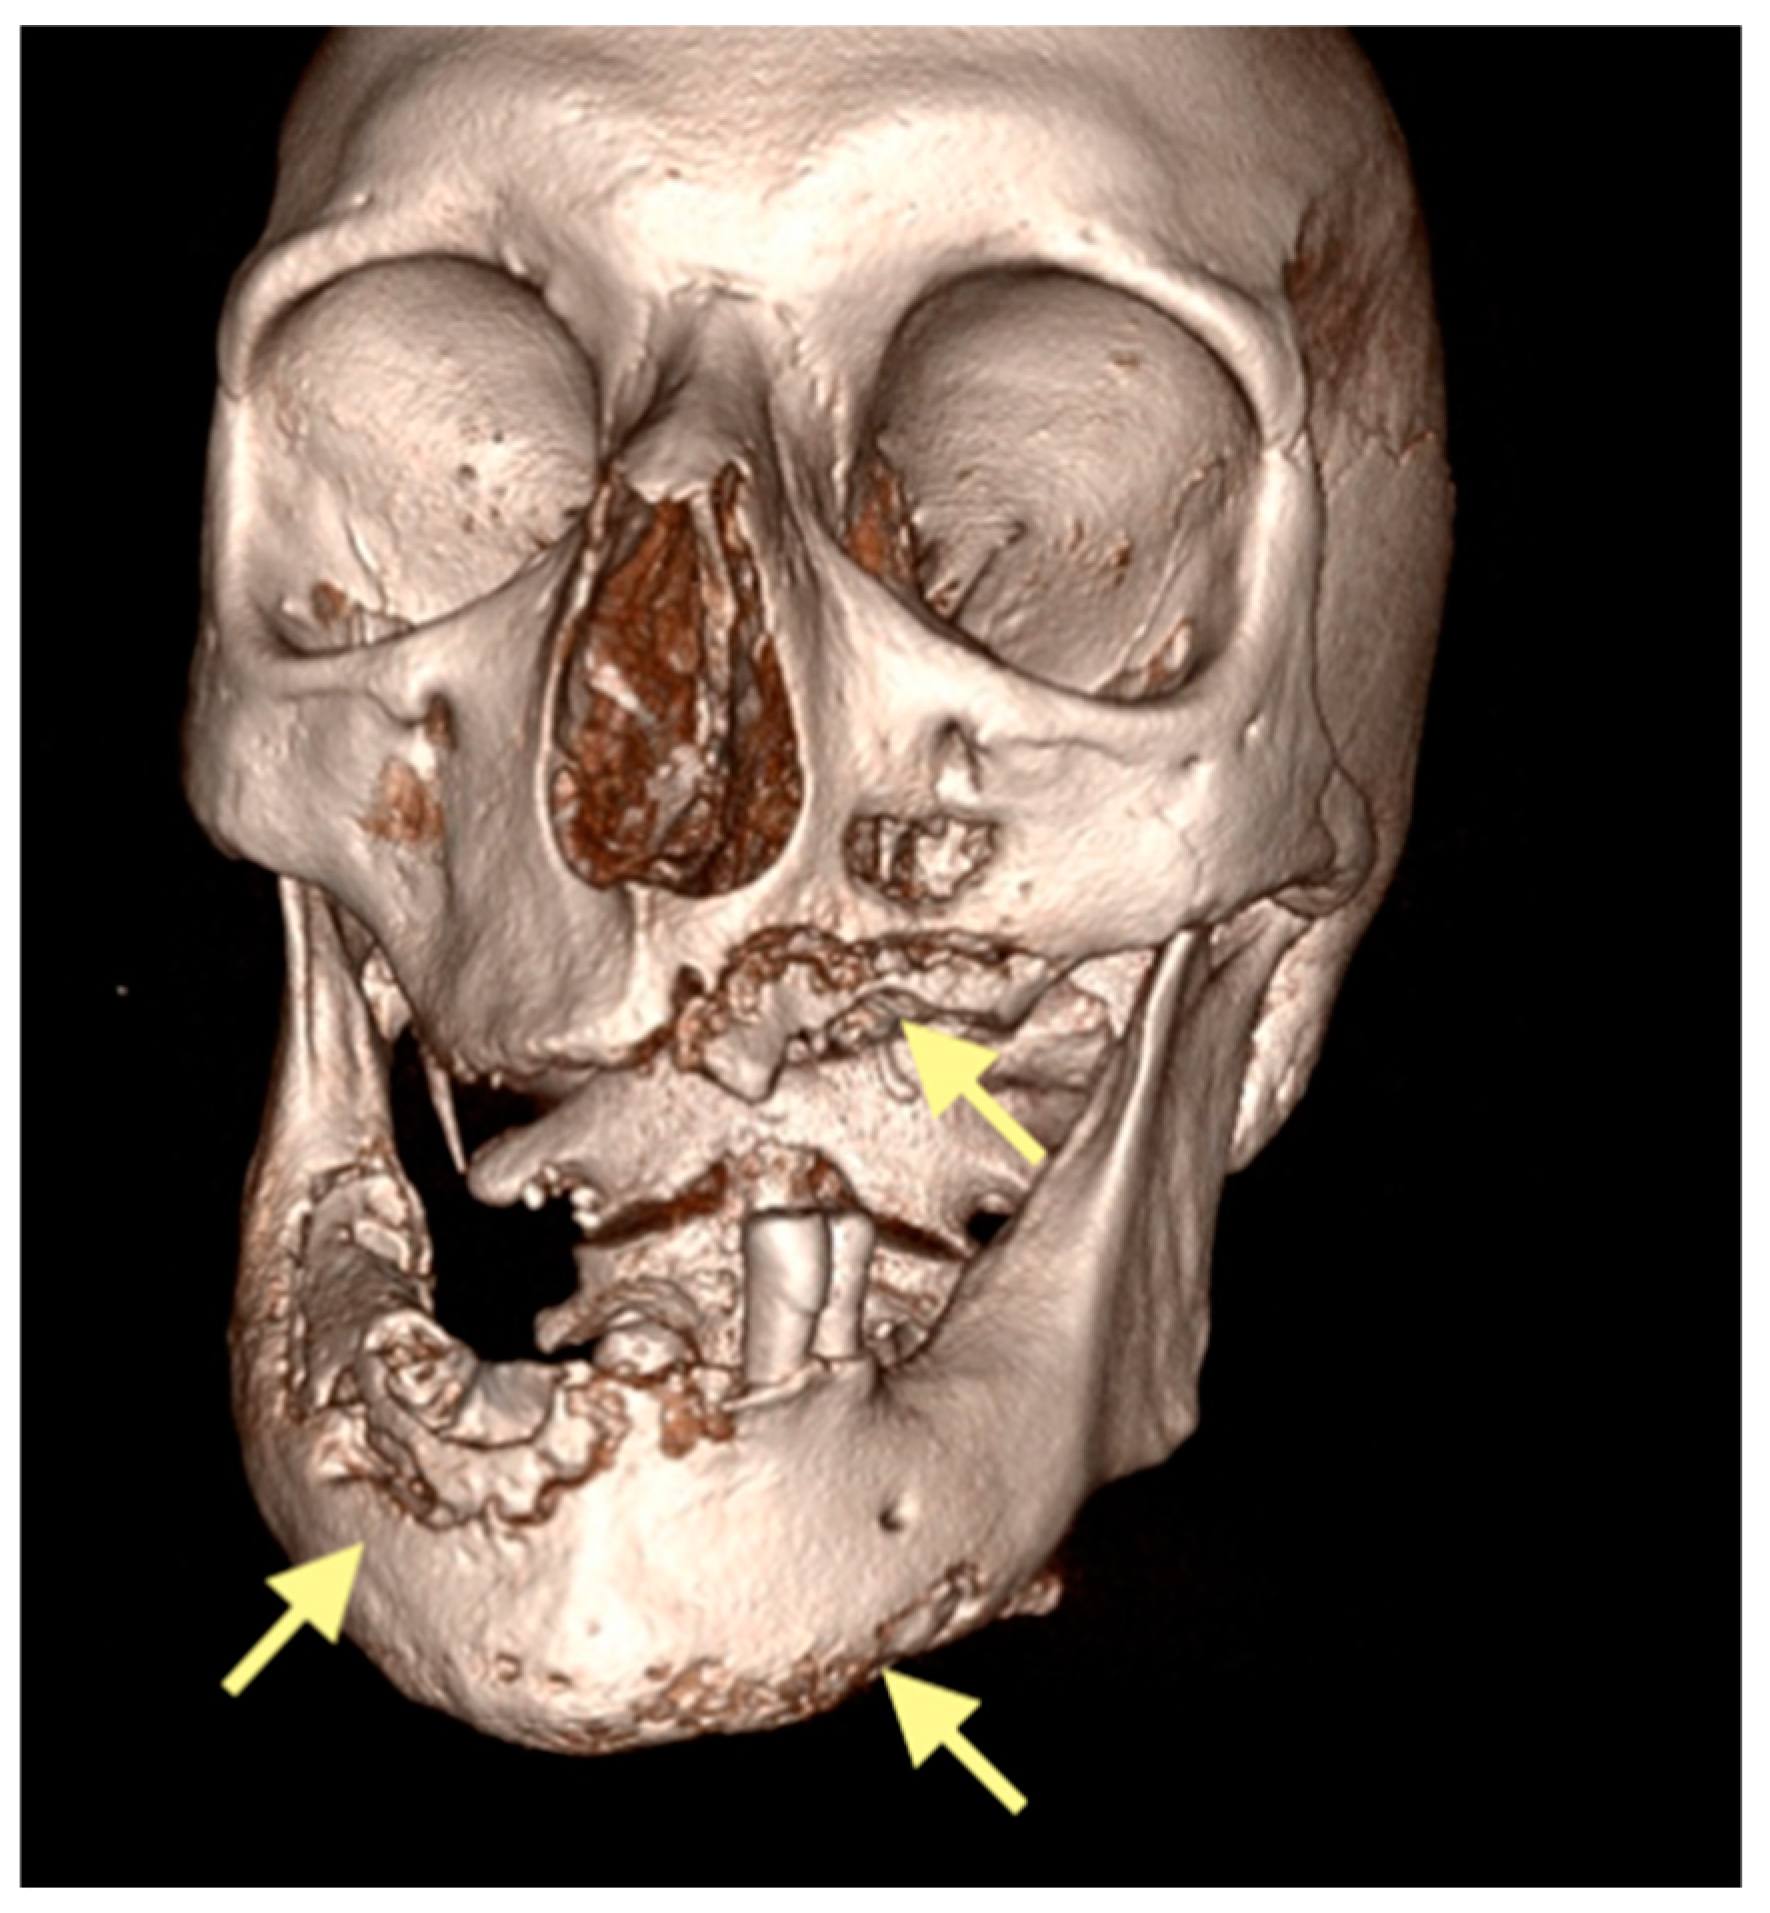

The third patient was a 75-year-old female with osteonecrosis of the mandible and maxilla in the fourth and in the second quadrant (see Figure 7, Figure 8 and Figure 9). The patient had third-stage jaw osteonecrosis. In 2023, the patient was diagnosed with osteonecrosis of the upper and lower jaw caused by antiresorptive therapy (until August 2021, the patient regularly used Zolendronic acid; then, this drug was replaced by the RANKL inhibitor Denosumab). The treatment was periodically complicated by submandibular and submental abscesses. In addition, due to the progression of the underlying disease, constant courses in chemotherapy were administered. The patient underwent three operations, which included sequestrectomy of the jaw with simultaneous use of A-PRF, antrotomy with revision of the maxillary sinus, closure of the oroantral communication, and opening and revision of abscesses of the soft tissues (see Figure 10 and Figure 11)

Figure 7.

CT of the head and facial bones (16 December 2024).

Figure 8.

Figure 9.